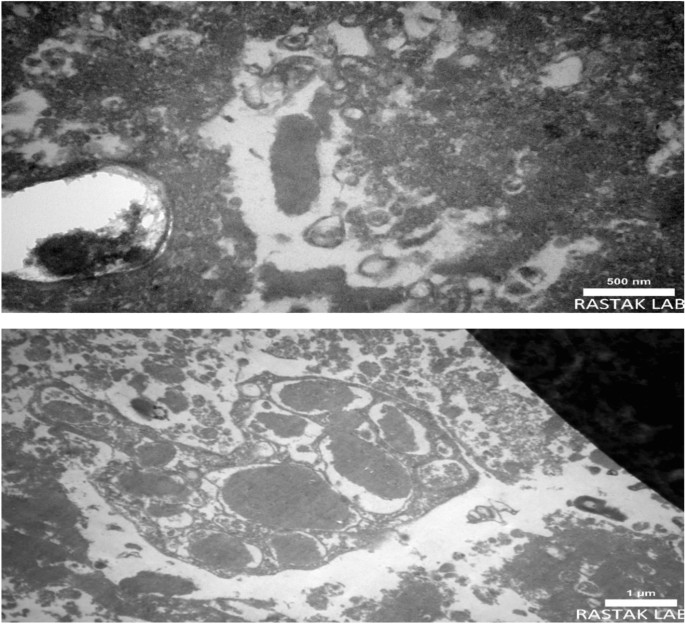

The heart valve samples that exhibited a positive result for Bartonella detection using the real-time PCR assay were chosen for examination in a transmission electron microscope. To increase the likelihood of observing bacteria by TEM microscopy, vegetative lesion-containing portions of the valve were selected. The fixed tissue samples were then dehydrated by dehydrated for 15–30 min in ascending ethanol concentrations of 30%, 50%, 70%, 80%, 90%, and 100%. Ultrathin sections of valve tissue (50–70 nm) were stained with 2% uranyl acetate and 0.1% lead citrate to visualize the bacteria in a Philips EM 208S microscope (Royal Dutch Philips Electronics Ltd., Eindhoven, The Netherlands)20.

Valve genomic DNA from that patient scored positive by qPCR, and the nucleotide sequence of ssrA gene was suggestive of B. quintana. Amplicons of the expected sizes were obtained also for other targets, as follows. The sample from patient No.10 showed the highest similarity with B. quintana MF1-1 strain for the gltA gene (100%) and the lowest similarity with B. quintana Toulouse strain for the ITS region f (99.4%). Conversely, a low degree of similarity was displayed with the gltA gene sequences of B. henselae strains (89.7%) and B. vinsonii subsp. berkhoffii (87.6%) (Fig. 2). Furthermore, Bartonella-like organisms organized in the form of invasomes were observed in the TEM micrographs of the patient’s aortic valve (Fig. 3).